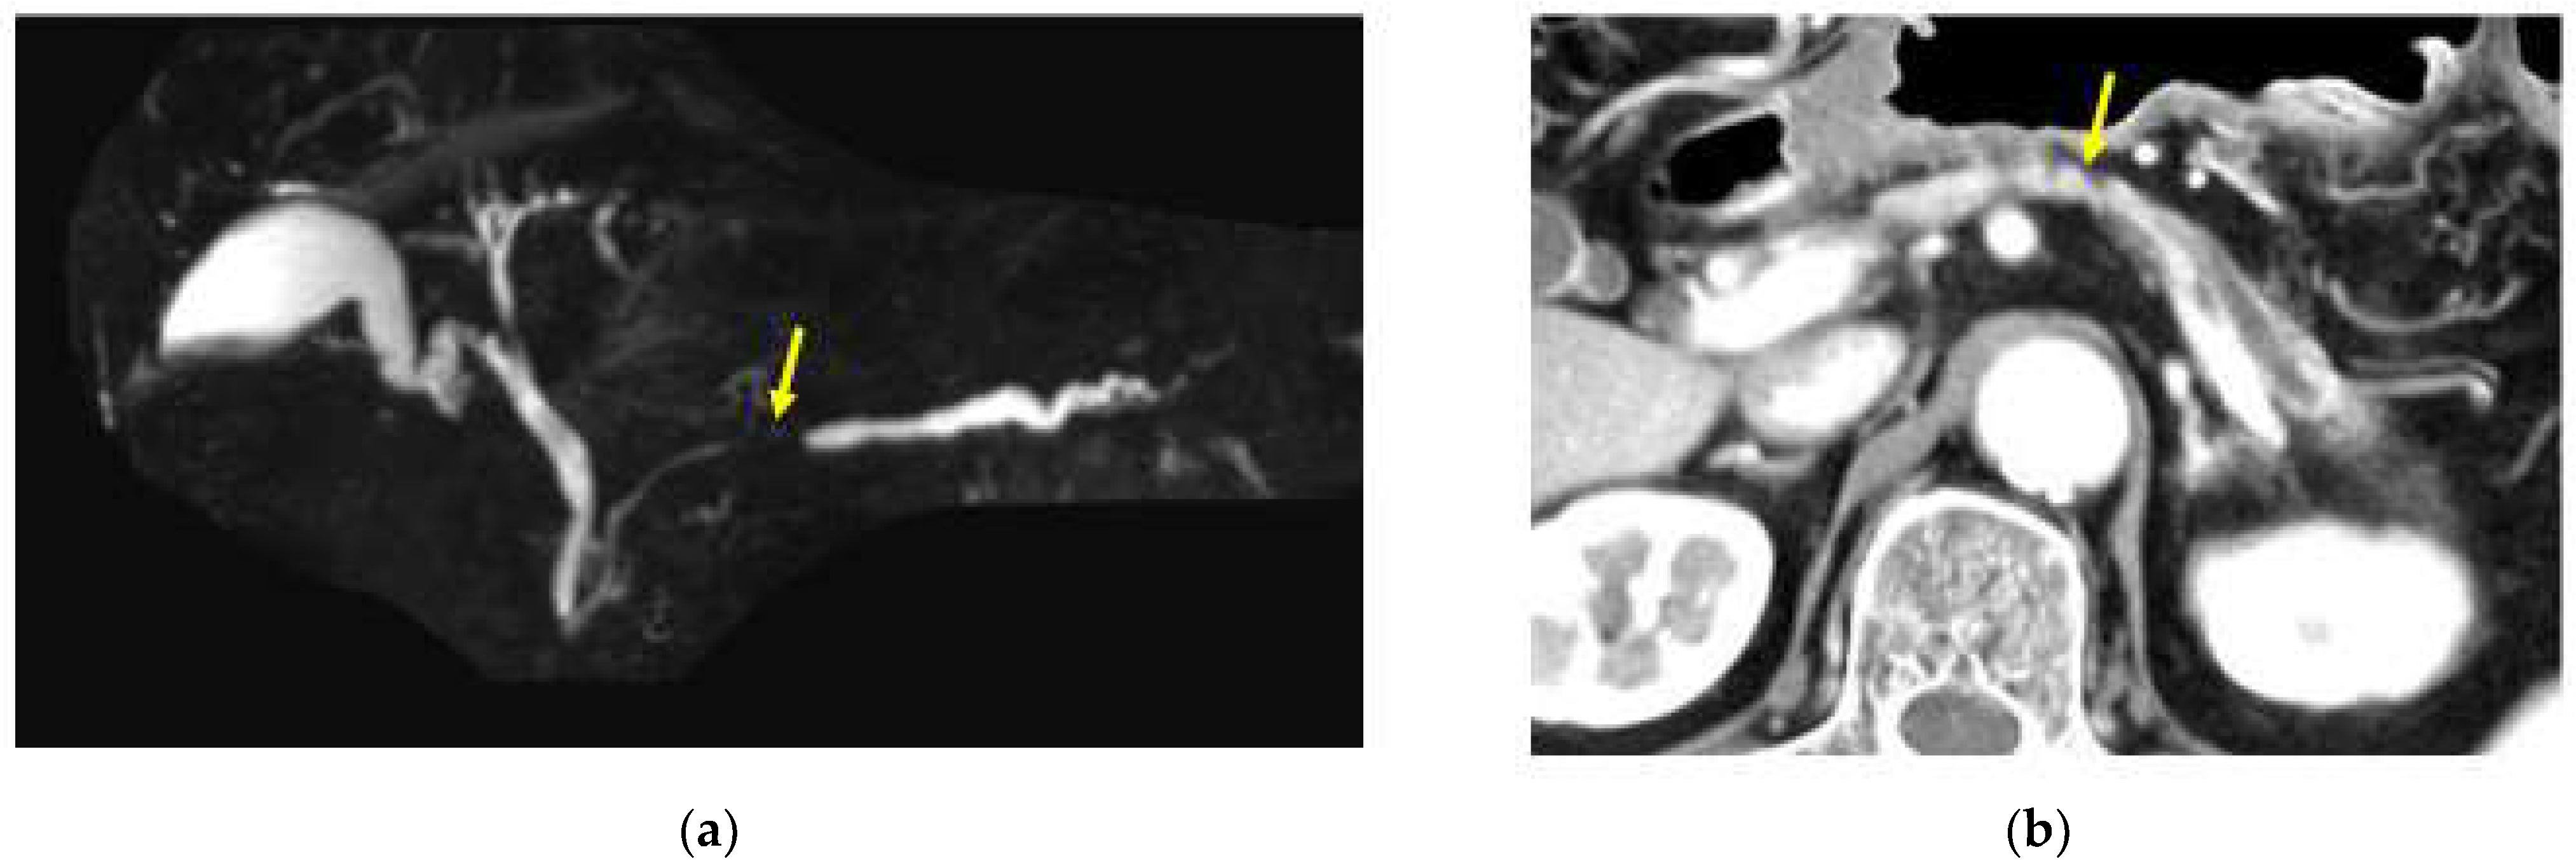

Figure 3.

A case in which no pancreatic tumor was found in the pancreatic body by CT or MRI imaging, but atrophy of the pancreatic parenchyma in the caudal part of the pancreatic body and dilation of the main pancreatic duct in the caudal part were observed, which were later diagnosed as in the body. (a) Magnetic resonance cholangiopancreatography showing stenosis of the MPD (red yellow arrow) and dilation of the MPD in the caudal part. (b) Enhanced CT showing the localized atrophic change (yellow arrow) in the pancreatic body and the dilation of the main pancreatic duct (MPD) in the caudal part.